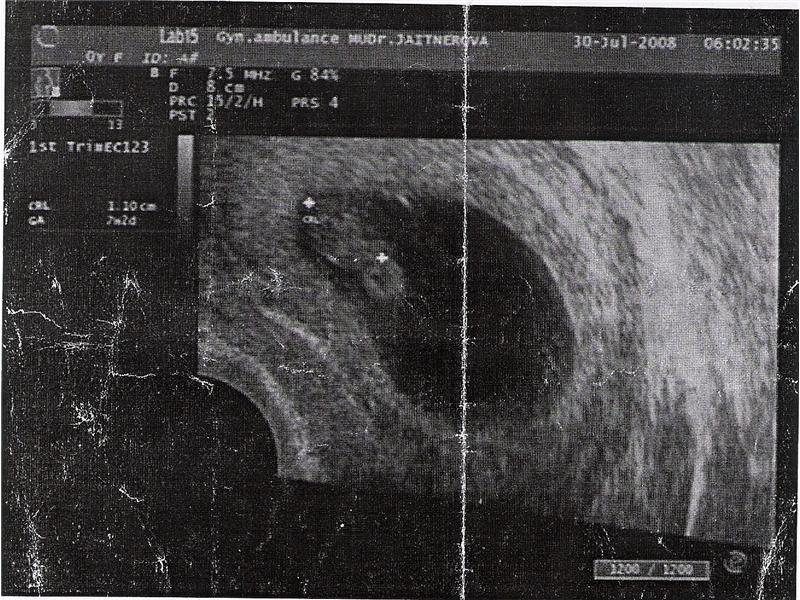

postupný vývoj našeho broučka